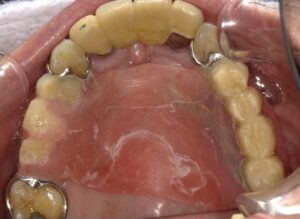

入れ歯ですとこのように針金があり、またピンクの部分が

とても違和感があります。

その点、インプラントは違和感が少ないといえます。